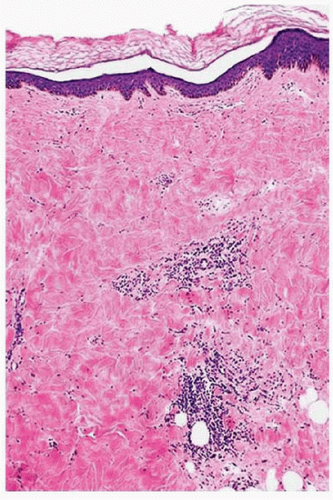

![]() FIGURE 3-3 Morphea late histology—increased dermal collagen with loss of blood vessels, adnexa, and fat. |

and the dermis and subcutaneous fat are replaced by thick, pale sclerotic collagen bundles (Fig. 3-3). Dermal appendages and blood vessels are replaced by collagen.